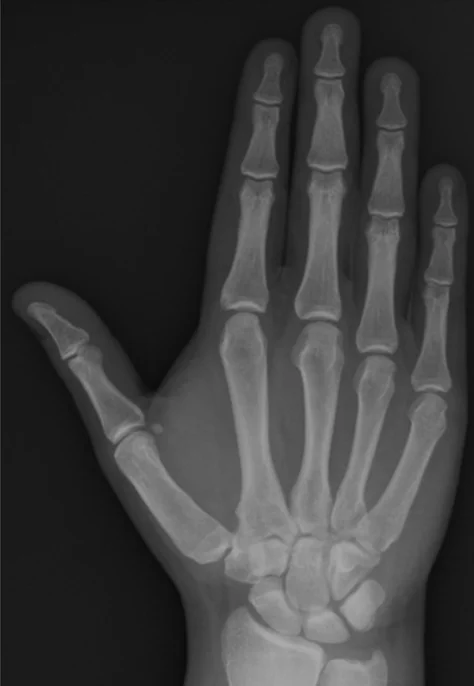

x-ray of hand

Reading Joints

- Name of joint

- Bone and Joint Alignment

- Position / Relations

- Joint space

- Articular surfaces